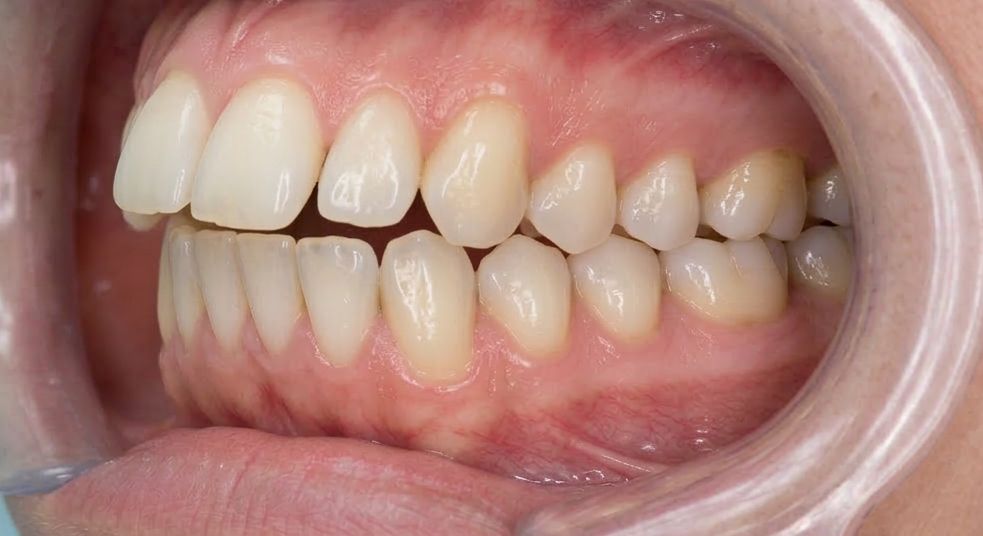

抜歯後3ヶ月時の口腔内写真

患者様は歯の欠損による見た目の問題、噛む能力の低下の問題とブリッジの土台を抜歯した場合、今回のように欠損歯数が増えてしまい、残っている歯に過剰な負担がかかり、さらに歯の欠損が増えていってしまう可能性が上がる問題などを考慮し、インプラント治療にて欠損部を補うこととしました。